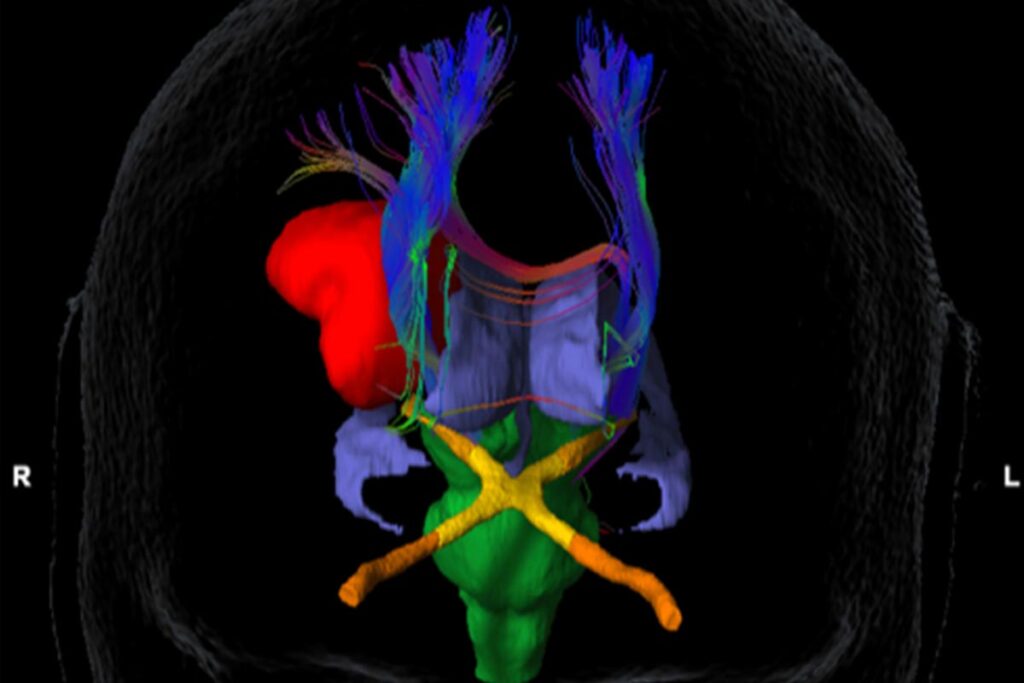

Hjernen styrer mange av kroppens funksjoner. Det finnes en rekke sentra i hjernen og disse er forbundet med nervebaner (nervefibre). Det går signaler ut til kroppen og det kommer signaler tilbake til hjernen. Hjernens funksjon kan påvirkes av både svulsten i seg selv og av behandlingen. Bildet viser en hjernesvulst (rødt) som ligger tett opp til motoriske baner (mørkeblått) og synsapparatet (gult).